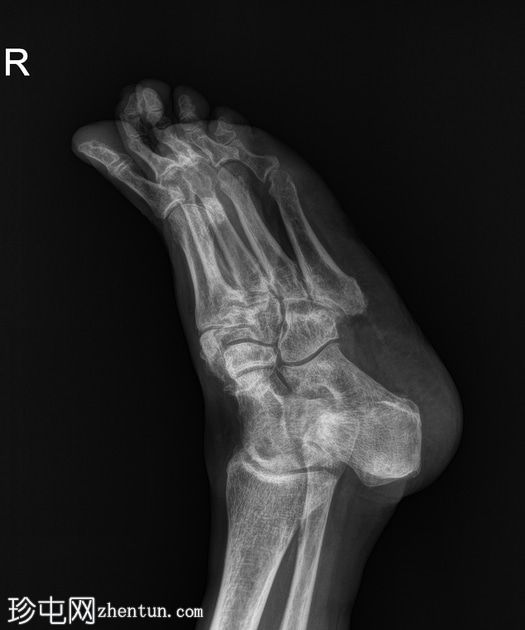

斜位片

双足均符合典型的夏科氏关节病特征,该患者为已知糖尿病患者。

该病表现为骨质疏松、骨硬化(密度改变)、跗骨碎裂和破坏、关节内游离体(碎屑)、软组织肿胀和关节积液(扩张)、中足结构紊乱以及跗跖关节错位(脱位)。

X线平片未见气性坏疽或化脓性关节炎的证据。

右足足底跟骨可见退行性骨刺和附着点病变。